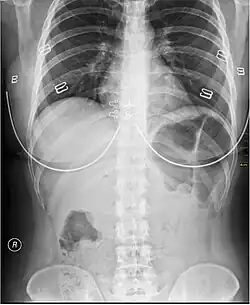

Röntgenfoto waarop meerdere artefacten te zien zijn, toe te schrijven aan een beugelbeha. -